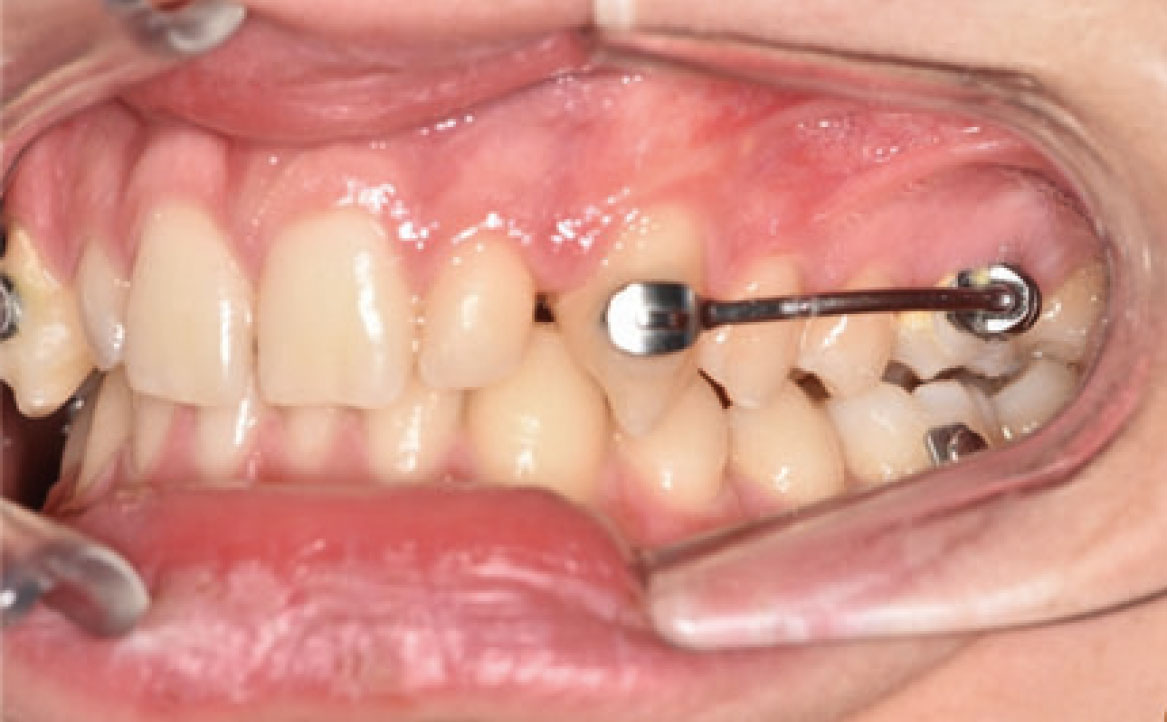

Un mese dopo, durante il secondo controllo, è stata raggiunta la posizione dei molari richiesta e, di conseguenza, il Carriere Motion è stato sospeso e si è iniziato il trattamento di ortodonzia fissa (fig. 4a-c).

Nello specifico, sono stati eseguiti bandaggi superiori e inferiori con tecnica Damon per l’allineamento e il livellamento delle arcate dentarie con l’aggiunta di rialzi occlusali, al fine di aprire il morso, ed elastici di classe II a tempo pieno (fig. 5a-c).